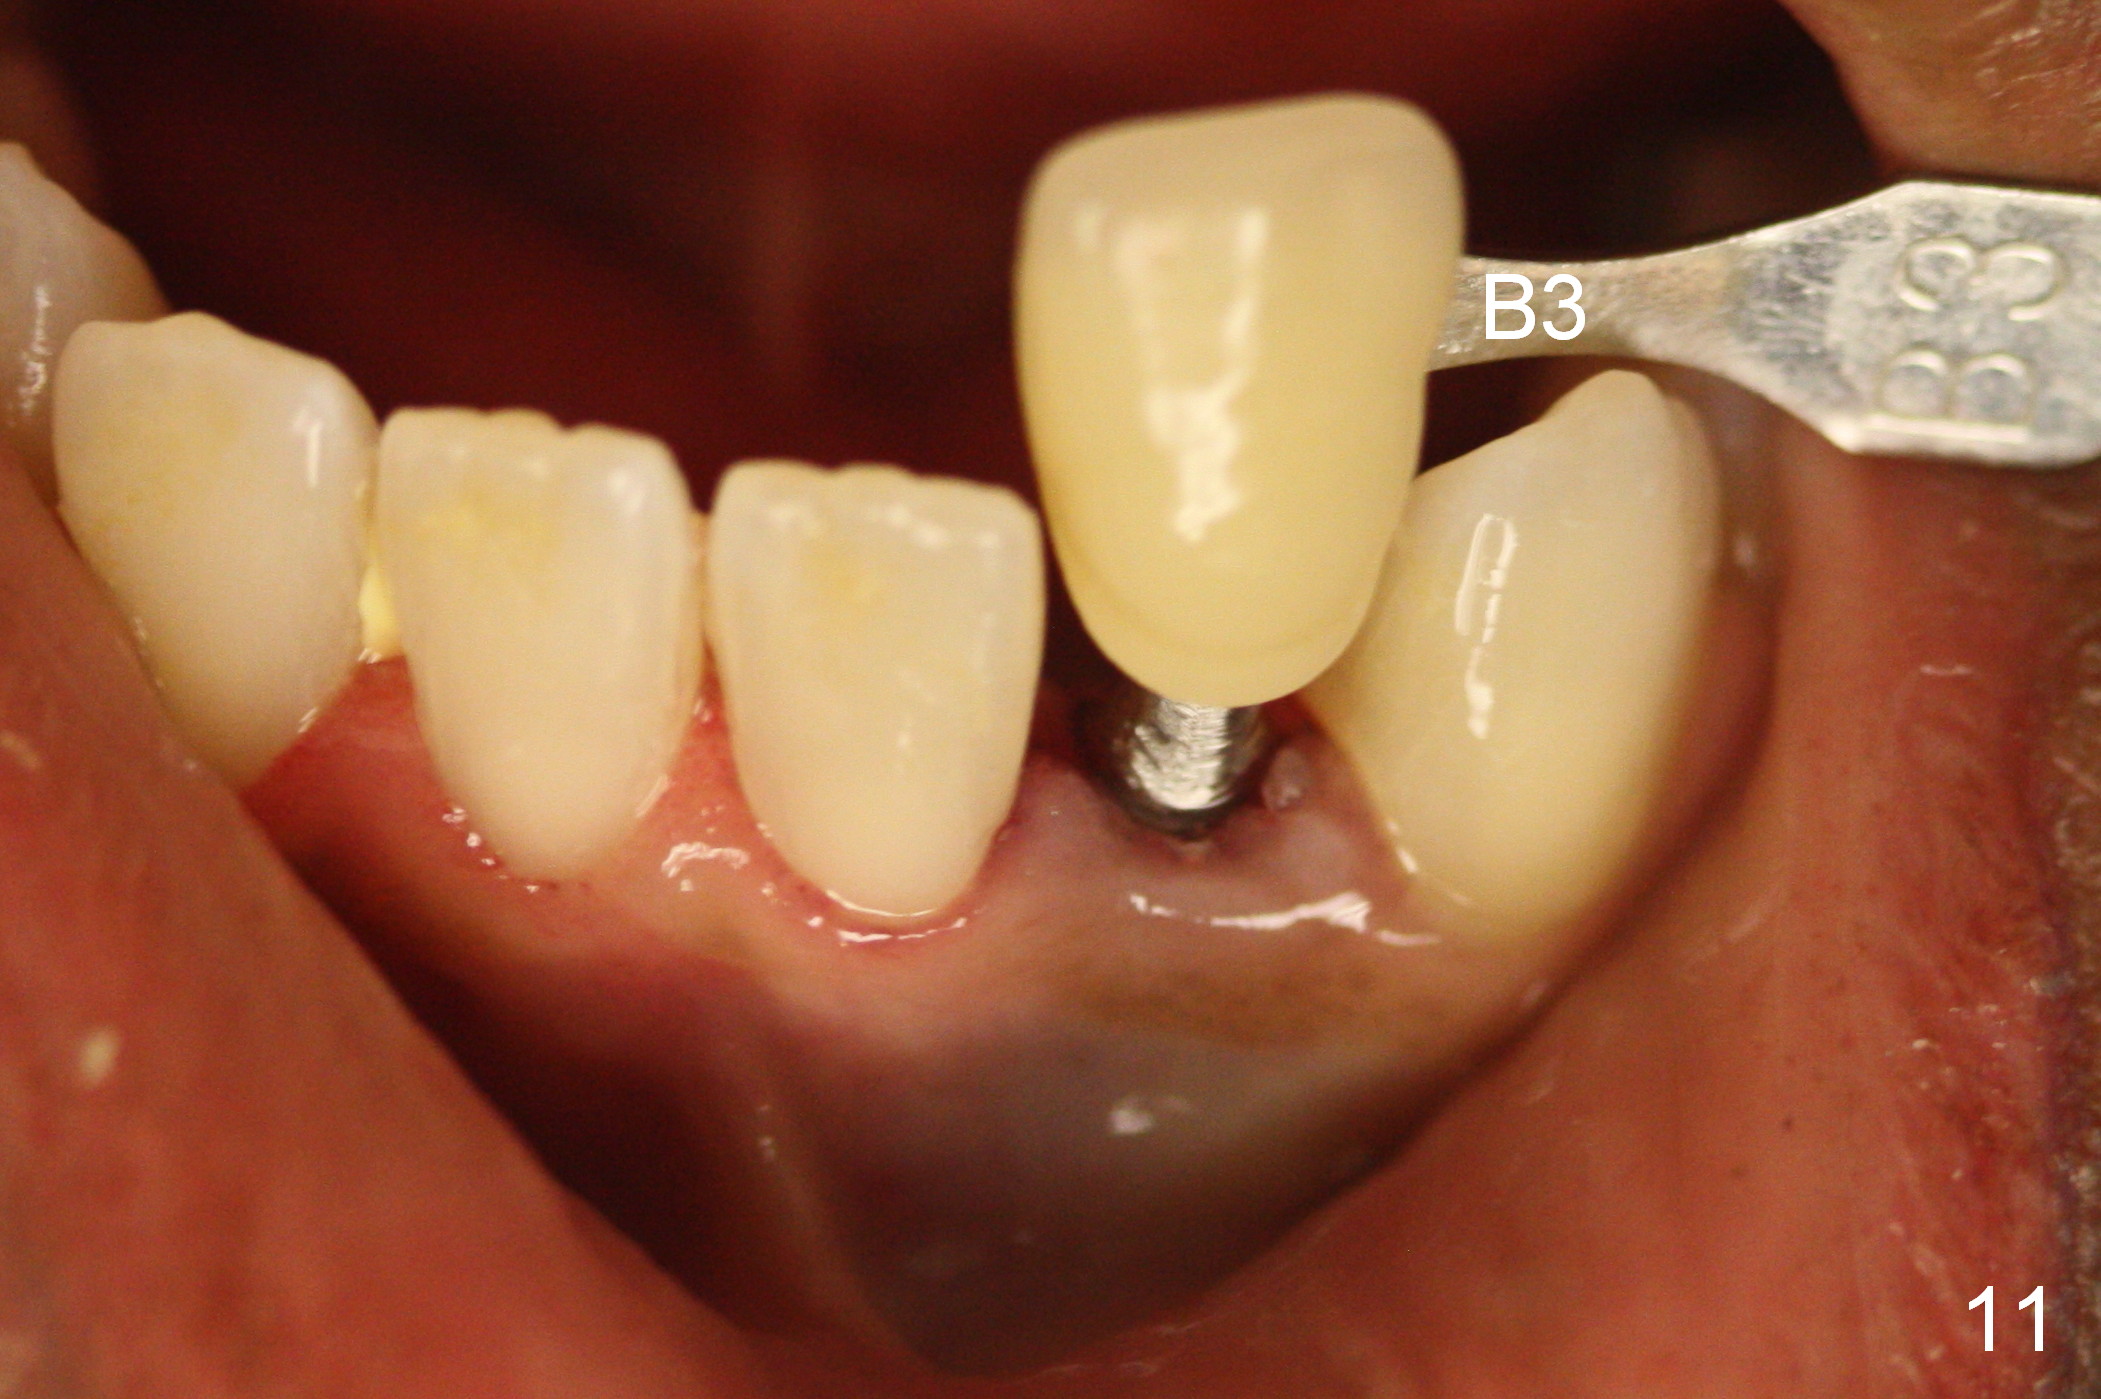

Suggestions for #23 implant crown redo (Fig.1, 2)

Make a new crown less transparent than the previous one (Fig.3). Can you block inside the crown to take care of the metal shade of the abutment/implant?

The original shade is A 2.5 (enclosed in the case).

Choose a shade a little darker and more yellowish (Fig.4-7 before

cleaning; Fig.9-11 after cleaning). It

appears that there is a change in shade of crown over the time.

Can you choose a Zirconia block that has the closest shade?

Do not stain or paint the crown.